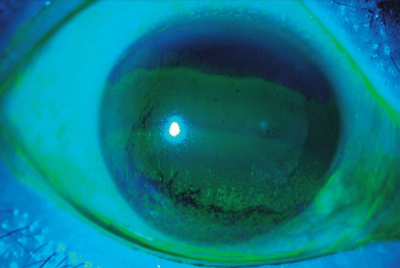

視力は右 1.0(1.2× -0.5 D) 、左 0.8(1.2× 1.0 D)。眼圧は右 15 mmHg、左 16 mmHg。瞳孔は正円同大で、対光反応は正常。Schirmer 試験は右5mm、左4mm(基準 10〜15) 。フルオレセイン染色後の細隙灯顕微鏡写真を別に示す。

治療として適切な点眼薬はどれか。